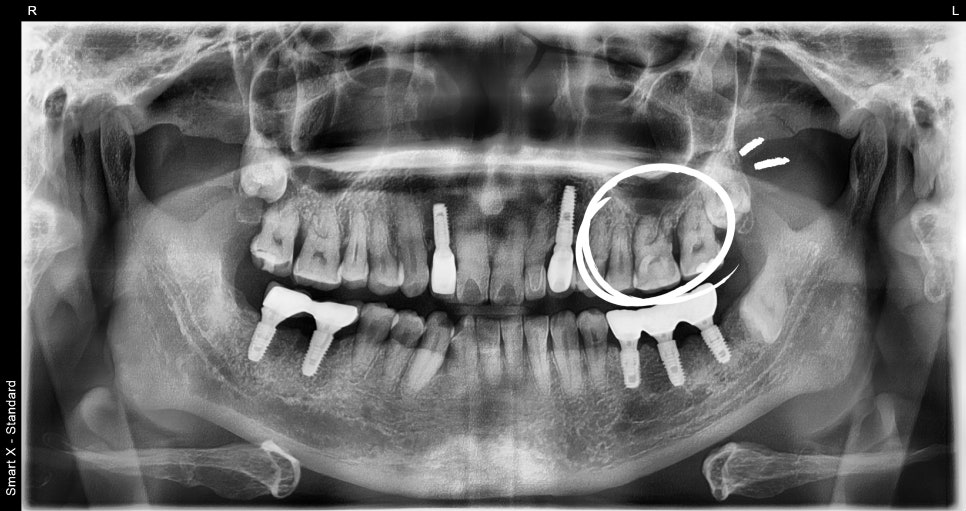

초진 내원당시

이번 케이스는 68세 남성 환자로, 잇몸이 심하게

붓고 통증이 발생한 상태에서 내원하셨습니다.

기존에 약을 복용하셨지만 증상이 호전되지 않았고,

어금니 부위의 통증이 점점 심해지는 상태였습니다.

검사 결과 어금니 주변 잇몸 내부에 고름이 형성된

치주농양 상태였으며, 뿌리 주변 뼈가 손상된 상태가

확인되었습니다.